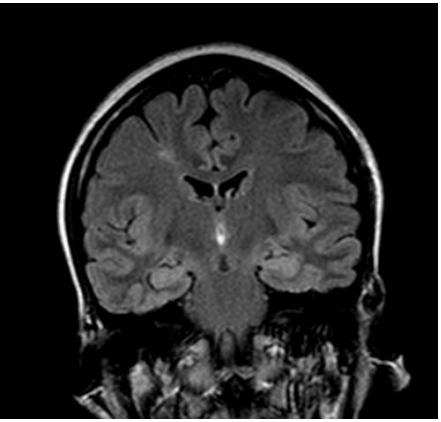

Figure 2: 65-year-old patient with anti-LGI1 encephalitis (seropositive). Cerebral MRI, FLAIR sequence: bilateral amygdalo-hippocampal hyper signal.

Brain MRI often objectified parenchymal abnormalities (86.7% of cases), which were similar to those reported in the literature [25, 51], including isolated temporal lesions (36.6% of cases). They were more bilateral than unilateral. Extra limbic radiological abnormalities were found in half of the cases. The most affected localisations are mainly the frontal lobe, the basal ganglia, and rarely other structures, such as the insula, parietal lobe, occipital lobe, meninges and white matter are affected. These extra limbic anomalies have been reported in the literature at a lower frequency than ours (40% of cases) [51]. Graus et al. included bilateral temporal involvement (in T2 and FLAIR) in the criteria for defined autoimmune encephalitis [23]. Unilateral temporal impairment would be possible. However, in this case, Graus et al. required the presence of antibodies to classify it as autoimmune encephalitis because other etiologies, such as glioma, seizures, and HSV1, could cause a unilateral temporal hyper signal [23].